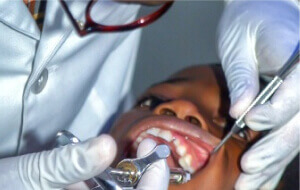

ODONTOLOGÍA

Ofrecemos soluciones adaptadas a tus necesidades: Aparatos fijos (Brackets metálicos o de zafiro) o aparatos removibles (Alineadores invisibles).